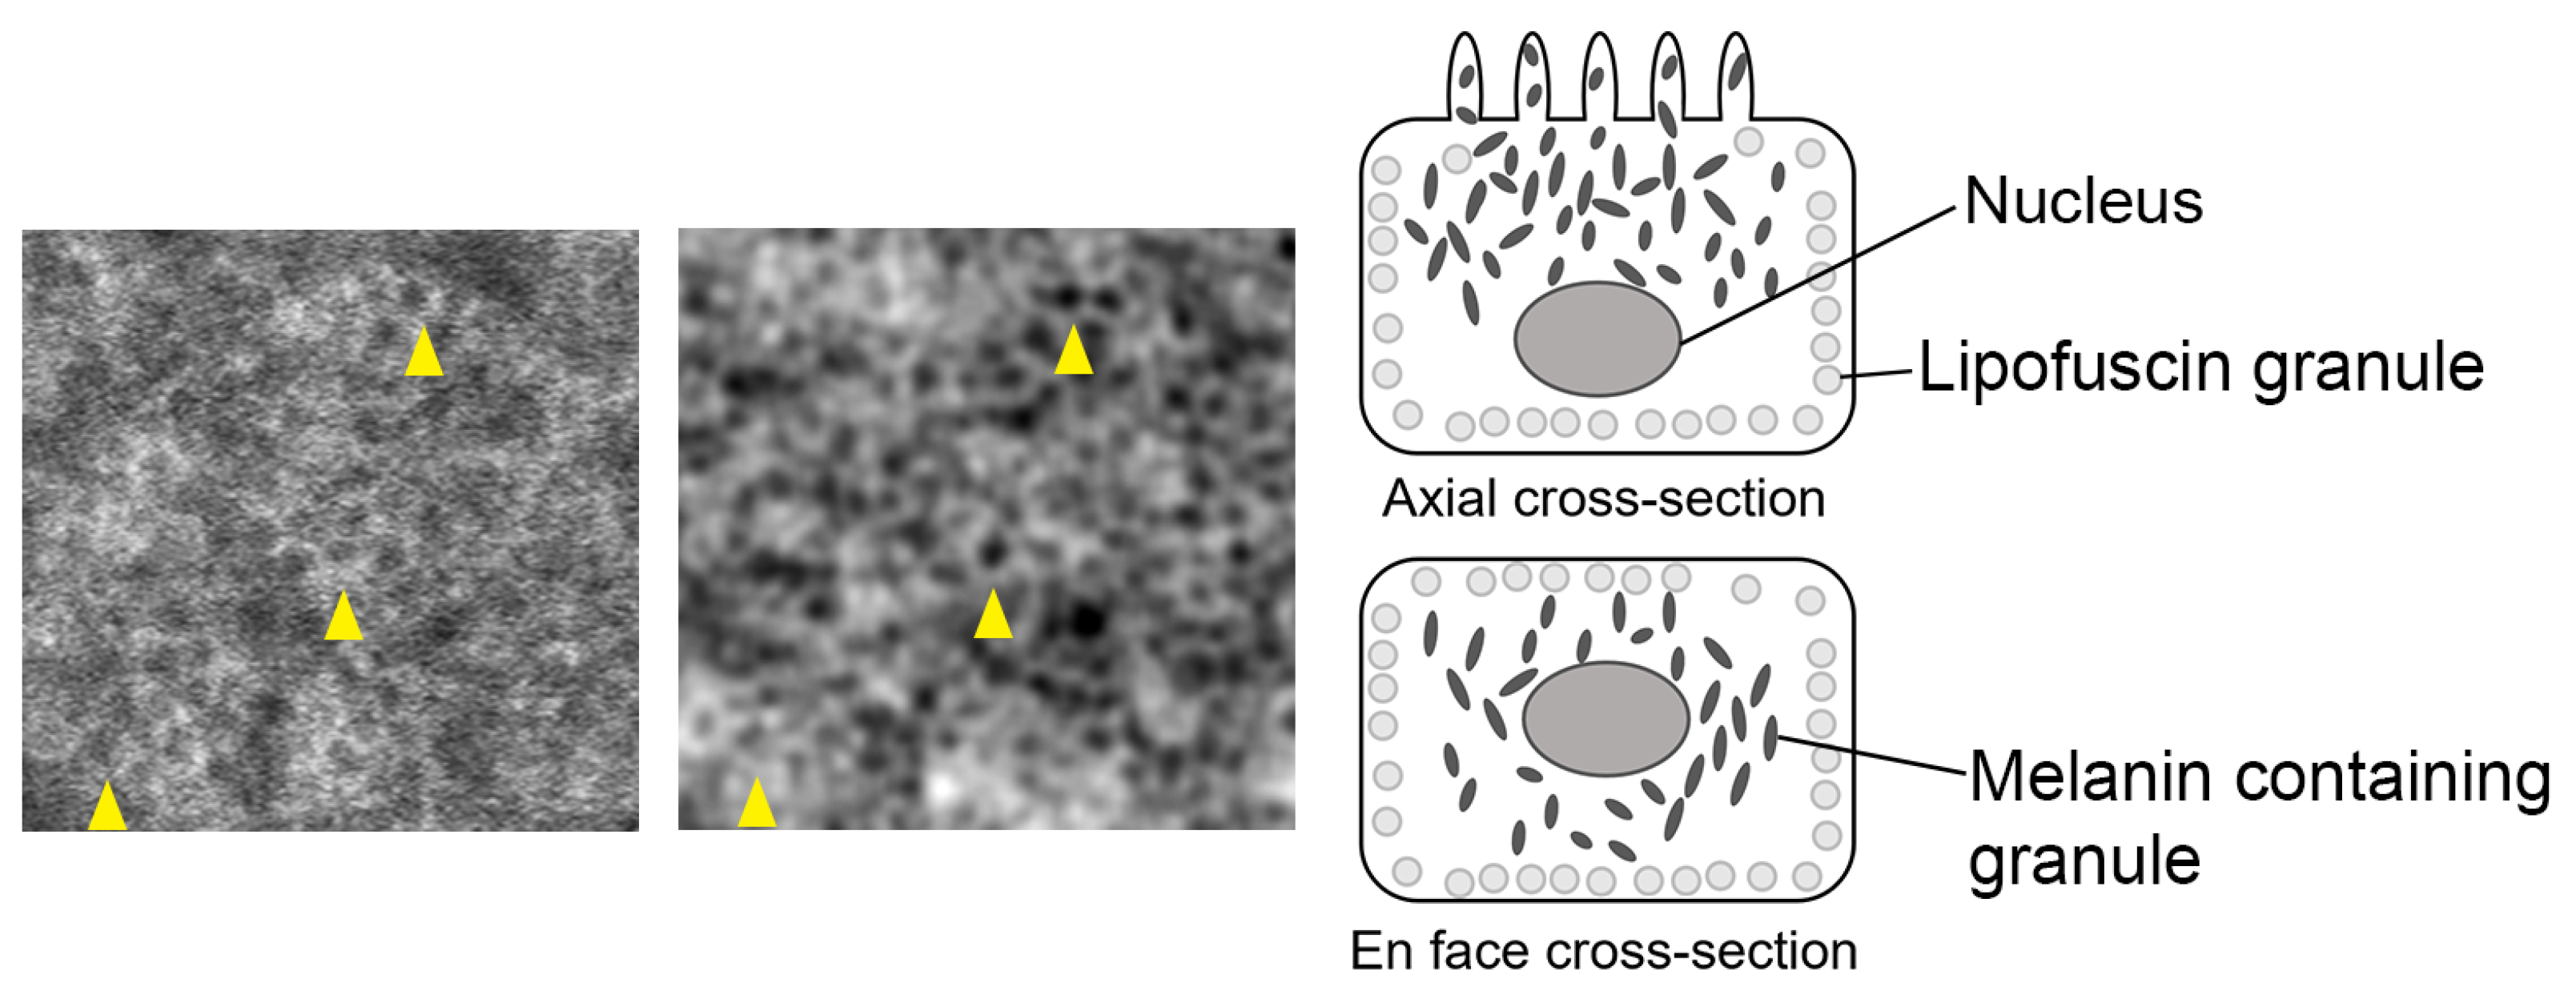

4.1. Origin of RPE Cell Contrast